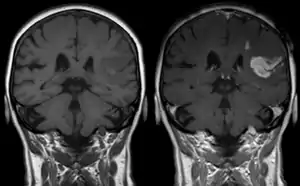

![]() | |

| T1 MRI of an ischemic stroke in the brain without (left) and with (right) contrast. | |

Diagnosis

Diagnosis of a cerebral vascular accident begins with a general neurological examination, used to identify specific areas of resulting injury. A CT scan of the brain is then used to identify any cerebral hemorrhaging. An MRI with special sequences called diffusion-weighted MR imaging (DWI), is very sensitive for locating areas of an ischemic based stroke, such as a watershed stroke.